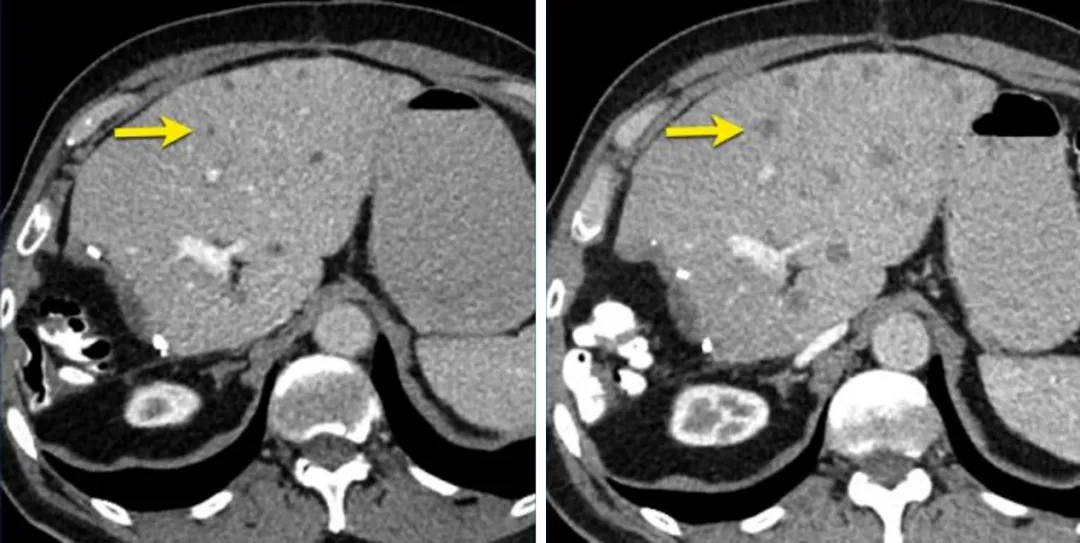

一名73岁男性结直肠癌并肝转移患者,后续随访CT显示肝内非靶病灶发生了进展,

即使其他病变达到PR或CR,该患者依然属于疾病进展。